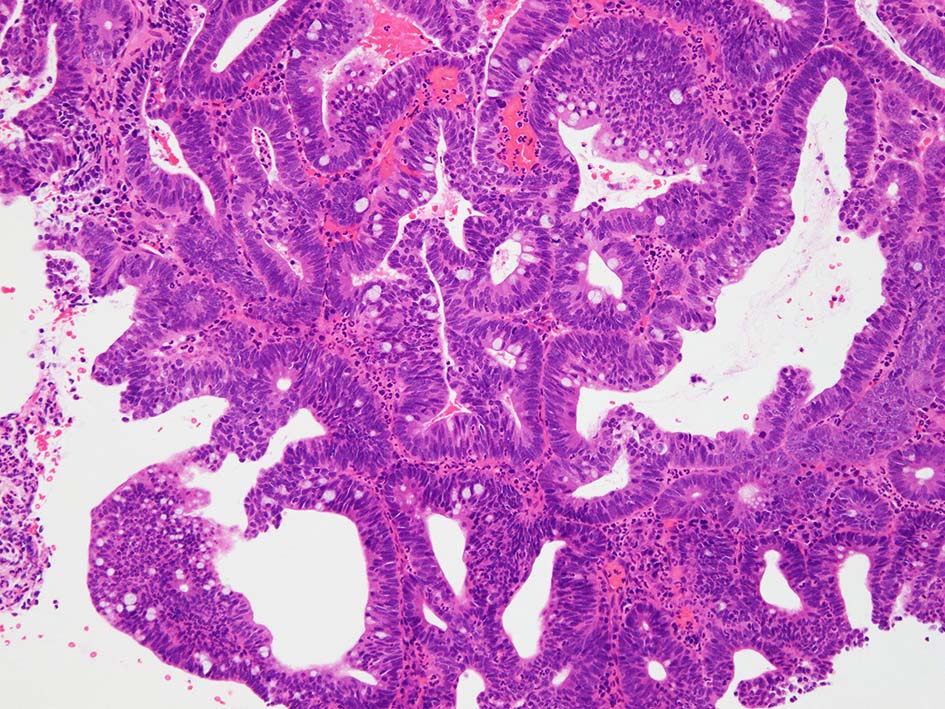

膀胱原発腺癌は隣接臓器, 特に結腸に発生する腺癌と診断上混同される。組織学的には, 様々な組織学的パターンを伴う大腸(腸)型腺管形態が優勢である。形態学的特徴から大腸型腺癌(not otherwise specified)、粘液性、印環細胞型、透明細胞型、肝細胞型、混合型に分類される。*3*4

腸管型の腺癌。大腸の高分化腺癌と組織学的に区別は難しい.

GI tract, とくに大腸癌の膀胱浸潤/転移を最初に考えた.